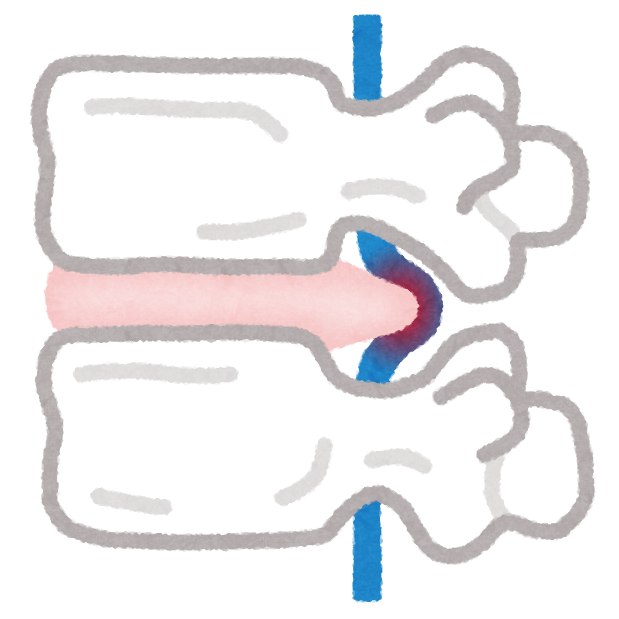

椎間板ヘルニア

3行で要約

椎間板ヘルニアは椎間板の中の髄核が逸脱して神経を圧迫した疾患

椎間板ヘルニアがあっても神経の刺激や圧迫がなければ症状が出ない場合も多い

治療には椎間板ヘルニアのある部位に負荷がかからないよう全身のバランス調整も必要

椎間板ヘルニアとは

椎間板ヘルニアとは脊椎と脊椎の間にある衝撃を緩和させるクッションのような役割を果たす椎間板という組織の中央にある髄核というものがなんらかの原因で本来の位置からズレた状態のことを言います。

髄核がズレるには髄核の周りにある線維輪という組織が何らかの理由によって変形や断裂を起こし、その結果髄核にかかる圧力バランスに乱れが生じて特定の方向にズレたり突出したりしてしまいます。

この線維輪の変形や断裂は椎間板に負荷をかけるような動作が多くなったり線維輪の柔軟性がある程度保たれつつも若年層に比べて低下している20代~40代くらいに多いとされ、ヘルニアの好発年齢もちょうどこのぐらいになります。

特に激しいスポーツや重いものを持ち上げようとして急激に力を掛けたりして椎間板にかかる圧力が急に高まったり、くしゃみのように瞬間的に強い圧がかかるようなことでヘルニア状態が起こりやすいとされています。

椎間板ヘルニアが起きやすいとされている部位は「腰椎の4番と5番の間」と「腰椎5番と仙骨1番の間」とされていますが、年齢が上がるにつれて腰椎の上部でも起きやすくなると言われています。

椎間板ヘルニアの症状について

椎間板ヘルニアでは上で説明したように髄核が正常な位置からズレたことで椎間板の一部が脊柱管内や椎骨の側面に突出することで突出した部位に存在する神経に圧迫や刺激が加わってしまい、局所やその神経の支配する領域に痛みや痺れといった症状が出現します。

例えば腰椎に椎間板ヘルニアが生じた場合、主に腰椎から出る神経の支配するお尻から足までの範囲に痛みや痺れが出ますのでいわゆる坐骨神経痛の症状も出現します。

ヘルニアになった直後は激しい痛みがでて歩いたり体を動かすこともままならないこともありますが、髄核の位置が落ち着いたり、体がある程度適応してくると症状も次第に軽くなっていきますが、線維輪の歪みや損傷と髄核の位置が正常に戻るわけではないので姿勢や疲労などによって神経の圧迫や刺激が加わるようになると再びヘルニアの症状が出てくるようになり慢性ヘルニアの症状へと移行していきます。

ただし皆様にご解しておいて頂きたいのは椎間板ヘルニアがあるからといって必ずしも椎間板ヘルニアの症状が出るわけではないといういことです。椎間板ヘルニアの症状はあくまでも神経の圧迫や刺激されることによって起きるもので、髄核の位置が正常ではないからといって症状が出ているわけではありません。実際に50代以上の人のほとんどにヘルニアがあるという調査結果が出ていますが、その中でヘルニアの症状がある方はごく一部とされていますので画像診断などによって椎間板ヘルニアがあるからといってすぐに痛みの原因は椎間板ヘルニアであると決めてしまうことは間違いです。

もちろん椎間板ヘルニアのある部位と症状の出ている部位が一致したり、他の検査等も併用することで明確に椎間板ヘルニアが原因で出ている症状であるとわかれば椎間板ヘルニアに対する治療が必要になります。